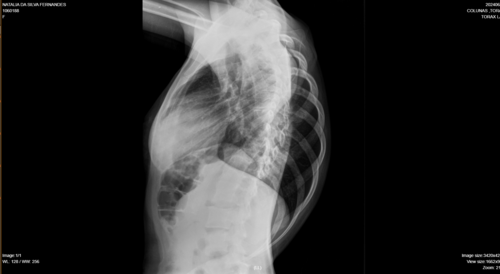

Olá, me chamo Natália da Silva Fernandes, tenho 21 anos, moro na cidade de Ji-Paraná, no estado de Rondônia. Fui diagnosticada com escoliose e venho na busca de um tratamento pelo SUS há um tempo, mas não obtive retorno até o presente momento. Passei por algumas consultas com ortopedistas do SUS, peguei encaminhamentos para passar com um neorocirurgiao e depois de um longo período de espera, consegui uma consulta com um neorocirurgiao do SUS, quando ele viu meu estado de saúde ele disse q a única solução é fazer a cirurgia, como na cidade não tem estrutura para realizar a cirurgia através do SUS, peguei mais um encaminhamento para consultar pela segunda vez por outro neurocirugiao, mas na cidade de Porto Velho, e nisso fiquei no aguardo desse agendamento mas até o momento nenhum retorno do SUS, ou seja, nenhum pedido de agendamento de cirurgia, apenas consultas, é um processo burocrático conseguir uma cirurgia pelo SUS, pois tem uma lista de pacientes na espera por vaga. Devido à demora do SUS , recorri a um neurocirurgião particular e o diagnóstico que recebi foi o mesmo, necessito fazer a cirurgia com urgência.Atualmente, me encontro num quadro doloroso, minha escoliose está com 86° de encurvatura, sinto dores constantes, tenho dificuldade em andar e às vezes dificuldade em respirar, porque são dores muito fortes. Para dormir, é uma luta constante para achar uma posição que dê menos desconforto . Diante de todo esse processo doloroso, e todo o tempo que venho recorrendo ao SUS e não obtendo uma solução favorável, a preocupação aumenta cada dia, pois não tenho condições de custear nem a cirurgia, nem o tratamento pós-cirúrgico. Foi então que surgiu a solução de fazer a vaquinha. A cirurgia fica em média de 250 mil reais com o tratamento pós-cirúrgico. Deixo na descrição os laudos e exames que venho realizando como transparência da minha situação.Toda ajuda é bem-vinda!Ajude-me compartilhando em suas redes sociais. Deixarei minha rede social para entrarem em contato comigo para mais informações: @_fe3_n47ou acesse o link abaixo e vá direto ao meu perfil.https://www.instagram.com/_fe3_n47?igsh=MXA1bDEzNW53YzZ5NA==